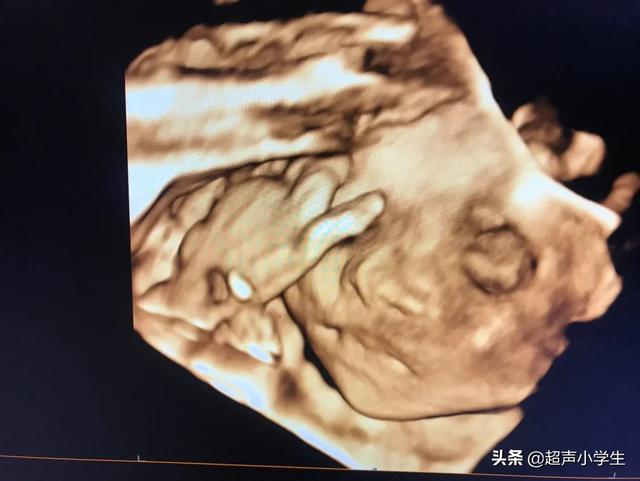

还有四维彩超可以记录宝宝的第一次有照片的容貌,也算是宝宝人生的第一张照片,运气好的话还是带微笑的照片,这个很有纪念意义。